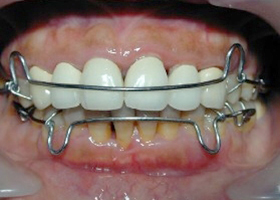

4.使用活動式矯正裝置矯正中(矯正方式因人而異)。

proimages/case/cosmetic/pic_case-025.jpg